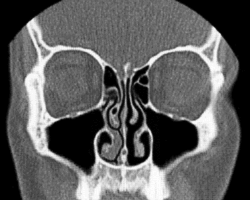

Según Heetderks, el ciclo es el resultado de la congestión y la descongestión alternas de los cornetes nasales, predominantemente los cornetes inferiores, que son, con mucho, los cornetes más grandes de cada fosa nasal. Los cornetes consisten en proyecciones óseas cubiertas por plexos cavernosos, que forman un tejido eréctil, al igual que los tejidos del pene y el clítoris. Los plexos venosos situados dentro de la mucosa que recubre los cornetes en una fosa se llenan de sangre mientras que los cornetes opuestos se descongestionan al ser desviada la sangre.[7]

Este ciclo, que está controlado por el sistema nervioso autónomo como se describe anteriormente, tiene una duración media de dos horas y media. Además observó y documentó que los cornetes en la fosa nasal dependiente se llenan cuando el paciente está en posición de decúbito lateral (acostado de lado). Algunos postulan que esta obstrucción posicional alterna tiene como propósito hacer que una persona gire de un lado al otro mientras duerme para evitar llagas.